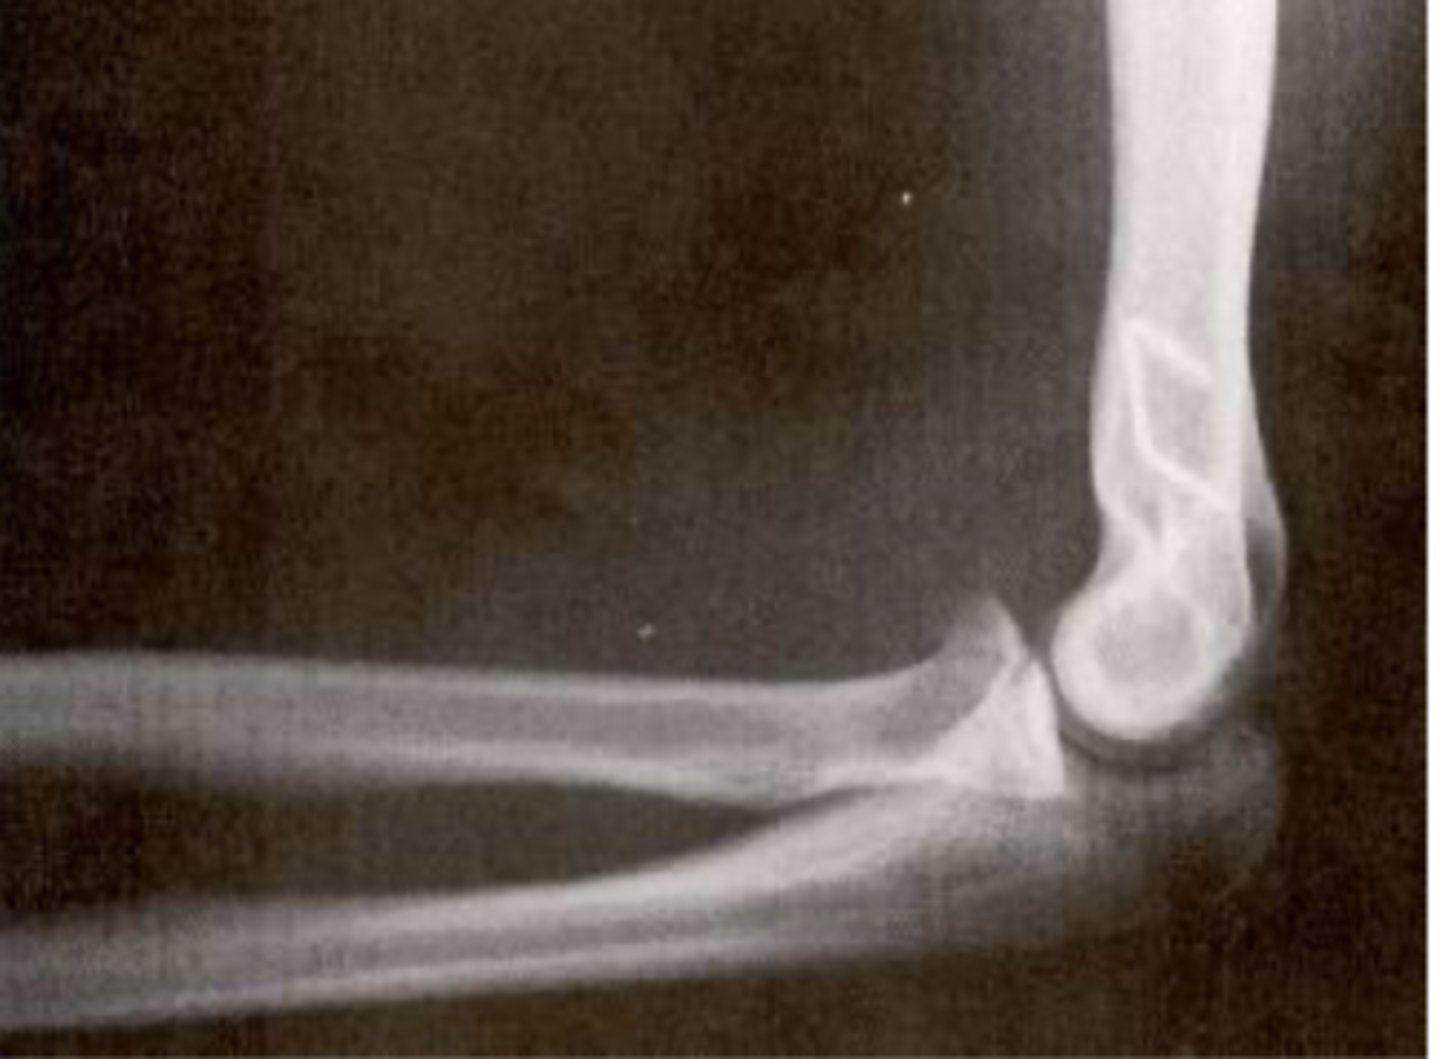

positive fat pad sign

What is the issue?